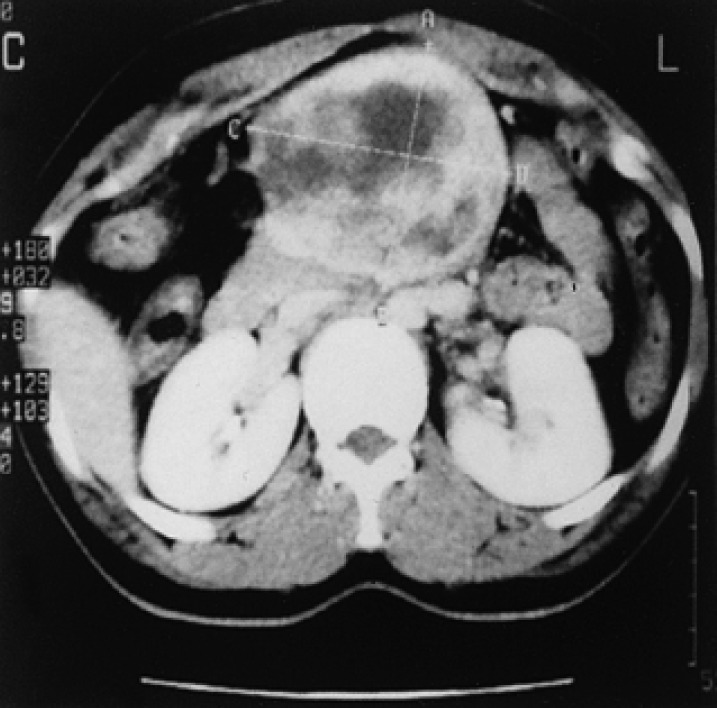

Figure 2

Abdominal CT scan of case I demonstrating a large (approximately 9×10 cm) inhomogeneous mass with an area of central necrosis.

Case I : A 31 year-old woman with a known neurofibromatosis was admitted complaining of a painful abdominal mass. A physical examination revealed a large, hard soft-tissue mass bulging out from the middle abdomen, and numerous, small subcutaneous neurofibroma nodules and brownish-pigmented lesions (café au lait spots) in the trunk and extremities (Figure 1). An abdominal CT scan demonstrated a large (approximately 9×10 cm) inhomogeneous mass with an area of central necrosis (Figure 2). The histopathology of the circumscribed and encapsulated mass obtained by a wide excision indicated a MPNST from the mesentery showing frequent mitoses in more than five per one high power field (Figure 3A). In the immunohistochemical stain, the tumor cells stained positively to the S-100 protein, which is a cytoplasmic marker used for identifying Schwann cells (Figure 3B). One month after surgery, the masses of the right paracolic gutter and the left supravesicle area appeared in the CT scan. The patient was then treated with 6 cycles of MAID chemotherapy (ifosfamide 2000 mg/m2 for 3 days, doxorubicin 20 mg/m2 for 3 days, and dacarbazine 300 mg/m2 for 3 days), which was followed by radiotherapy (5400 cGY). The masses began to disappear after chemoradiotherapy but the disease progressed 2 months later. She was treated with a further 6 cycles of VIP chemotherapy (etoposide 75 mg/m2 for 5 days, ifosfamide 1,000 mg/m2 for 5 days, and cisplatin 20 mg/m2 for 5 days), with a partial response being observed. However, she died as a result of disease progression 21 months after the initial diagnosis.